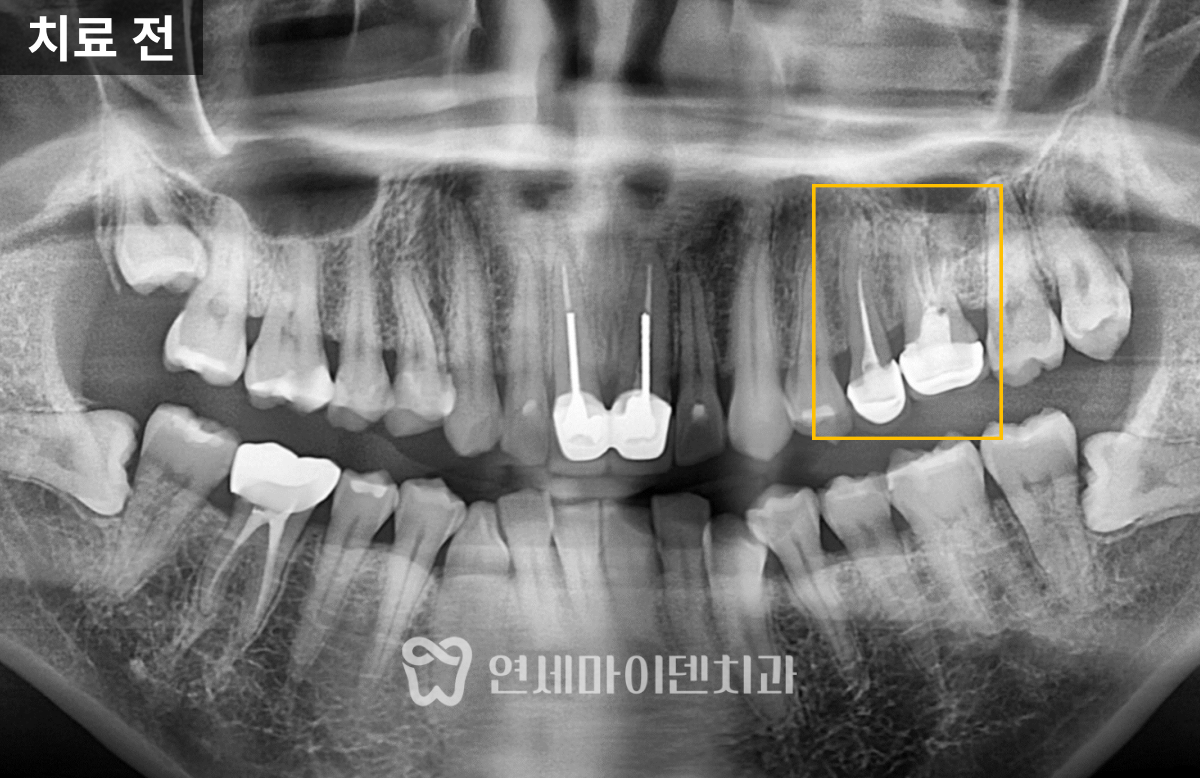

이 환자분은 '예전에 신경치료를 받았던 왼쪽 위 어금니쪽이 시린 증상이 있고 아프다'며 내원하셨는데요.

두 개의 치아 모두 불편함이 있었고, 모두 치료를 받은 지 꽤 되었으며, 염증이 있는 상태였습니다.

살펴보니 과거에 받으셨던 신경치료의 퀄리티가 아쉬운 부분이 있었습니다.

신경관뿌리까지 치료가 되어있지 않고, 중간에 갭이 보였습니다.

그리고 앞쪽 치아의 신경치료 방식을 보니 거타포차 콘(GP cone)을 하나씩 삽입하는 오래된 방식으로 이뤄져 있었습니다. 오래된 방식이라고 반드시 나쁜 것은 아닙니다. 다만 현재 훨씬 개선된 치료법이 존재하기 때문에 환자분들께서 더 완성도 높은 치료를 받으실 수 있습니다.

먼저 CT를 촬영하고 시작했어야 했는데, 나중에 CT를 확인해보니 구개측 뿌리에 퍼포레이션(뚫림)이 발생해 있었습니다.

이 치아는 세개의 뿌리가 있는데, 구개측 뿌리의 신경관 중간부에 구멍이 뚫려있었고 그 부위의 뼈에서 염증으로 인한 출혈이 계속 올라오고 있었습니다.

뼈가 상당히 손실된 상태였습니다. 만약 뼈 소실이 심하기 전에 이 구멍을 MTA라는 특수 재료로 처치했다면, 치아를 살릴 수 있었을 텐데 그 시기를 놓쳐 뿌리 절제술을 하거나 발치 후 임플란트 중 하나를 선택해야 했습니다.